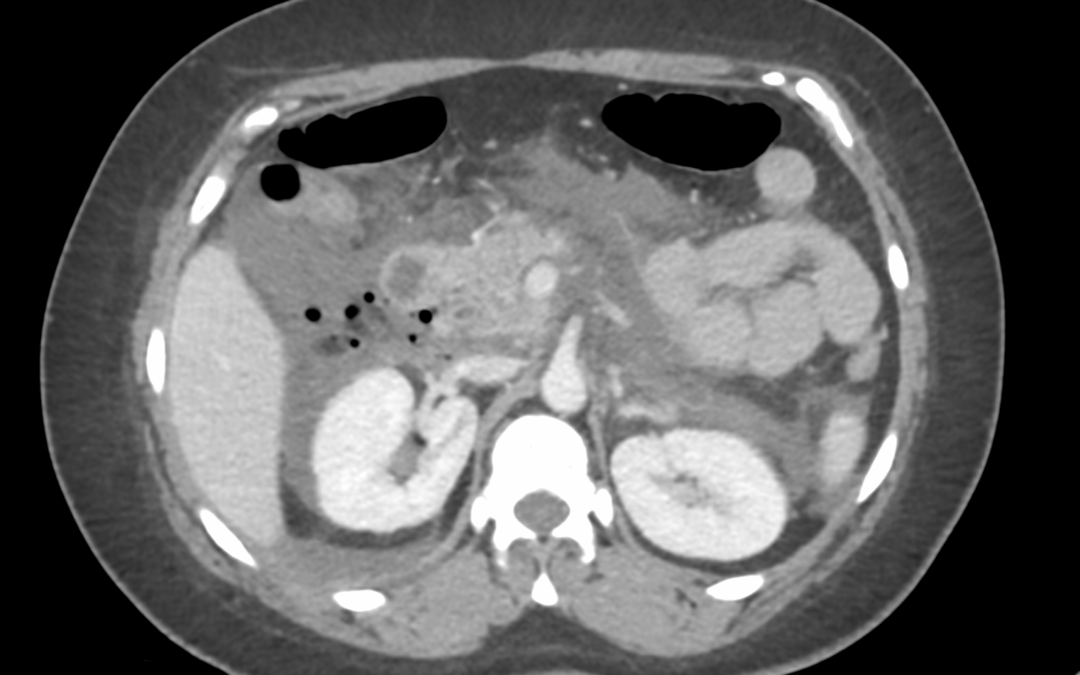

• Mujer de 35 años, sin antecedentes médicos de interés. No hábitos tóxicos. No toma tratamiento crónico. Colecistectomizada como único antecedente quirúrgico. • Ingresa para estudio de epigastralgia de un mes de evolución. No fiebre. Analíticas con elevación de...